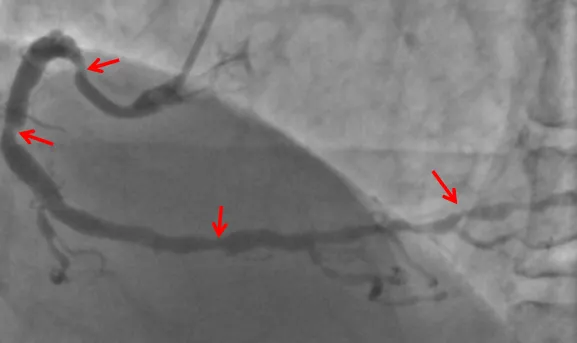

▲左冠脉主干严重狭窄,涉及到三分叉,风险高

然而最近一个月,张先生的胸闷症状发作越加频繁,发作时间甚至更长。在家人的陪同下,他前往医院进行检查,冠脉造影检查提示:左主干+多支血管病变,且冠脉病变弥漫、狭窄严重,主干分叉多,左边的前降支、回旋支和中间值仅遗留一丝丝血流供血,右冠脉全程弥漫性狭窄,远端也重度狭窄90%,诊断冠心病明确,且冠脉病变高危复杂,可以说是“心悬一线”。